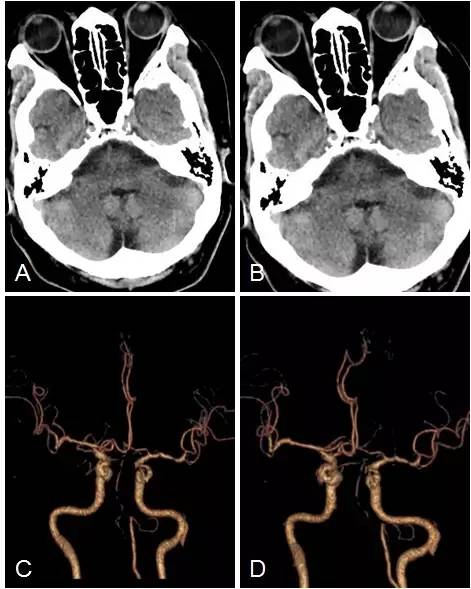

头颅CT+CTA:脑干及小脑半球多发梗死(图3A,B),双椎动脉V4段闭塞,基底动脉近段重度狭窄(图3C,D)。

图3